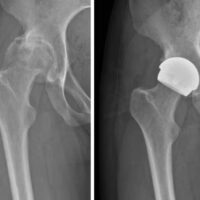

Surgeons at Cleveland Clinic London have begun performing hip resurfacing with ceramic implants. They are among the first in the world to provide this alternative to metal-on-metal hip resurfacing, which currently is recommended only for patients with larger femoral heads.

In response, Prof Cobb and a team of developers produced a novel ceramic hip resurfacing implant, the H1, designed for patients with smaller hips and a smaller pelvis. A 2023 clinical study found that women receiving the H1 had postoperative biomechanics similar to healthy women without hip surgery, while women who had total hip arthroplasty (THA) had worse biomechanics.

Following that publication, Prof Cobb and a team started working toward designing implants, first in metal and later in ceramic, contoured for smaller hips. After four years of preclinical testing to show safety and efficacy, clinical trials of the H1 ceramic implant began in 2017.

H1 hip resurfacing vs. total hip replacement

In 2023, Prof Cobb was senior author of a study in Gait & Posture comparing 15 women with H1 hip resurfacing and 15 women with conventional THA. Results indicated that, compared to patients having THA, those with the H1 implant:

- Reported significantly higher activity levels (per metabolic equivalent of task scores) after surgery (11.2 vs 7.1, P = .02)

- Recorded a faster and significantly improved maximum walking speed after surgery (6.8 km/hr vs. 6.2 km/hr, P = .003)

- Had a symmetrical gait at heel strike, midstance and push-off when walking at a fast speed (6 km/hr) after surgery (while patients with THA had an asymmetrical gait at all three points)

- Had a longer step length when walking at a fast speed after surgery (79 cm vs. 73 cm, P = .02)

In addition, patients with the H1 implant recorded a ground reaction force after surgery similar to people who didn’t have hip surgery, whereas patients with THA had a weaker push-off force.

“All patients had improved function after surgery compared to before surgery, whether THA or hip resurfacing with the H1 implant,” Prof Cobb says. “However, only those women with the H1 implant achieved postsurgical gait speed, symmetry and other elements of function comparable to people with healthy hips. Women with replaced hips had shorter steps, weaker force and more asymmetry after surgery compared with healthy controls — exactly as described in previous studies. In this study, the patients with resurfaced hips had functional levels indistinguishable from healthy controls, while the women with total hips were slower and had worse balance.”